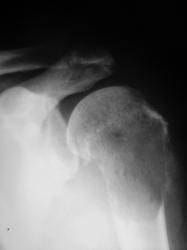

Нарушая все каноны обсуждения, но пользуясь тем, что Татьяна Валентиновна прокомментировала, хочу задать ей вопрос. Ваше мнение по поводу представленного ниже.

Хотела сразу написать "метастаз почечноклеточного рака". А если серьезно, Валентин Львович, подобная картина: литический очаг деструкции, со вздутием, разрушением коркового слоя, периостозом, требует морфологии, т.к. рентгеновская картина не специфична для какой-то определенной нозологии, диф. ряд включает и метастаз и первичную опухоль кости (прежде всего ходросаркома, остеосаркома, лимфома, ЗФГ).

Сам заключения не видел, но коллега терапевт информировал, что из областного ОД пришла гистология - "хондросаркома".